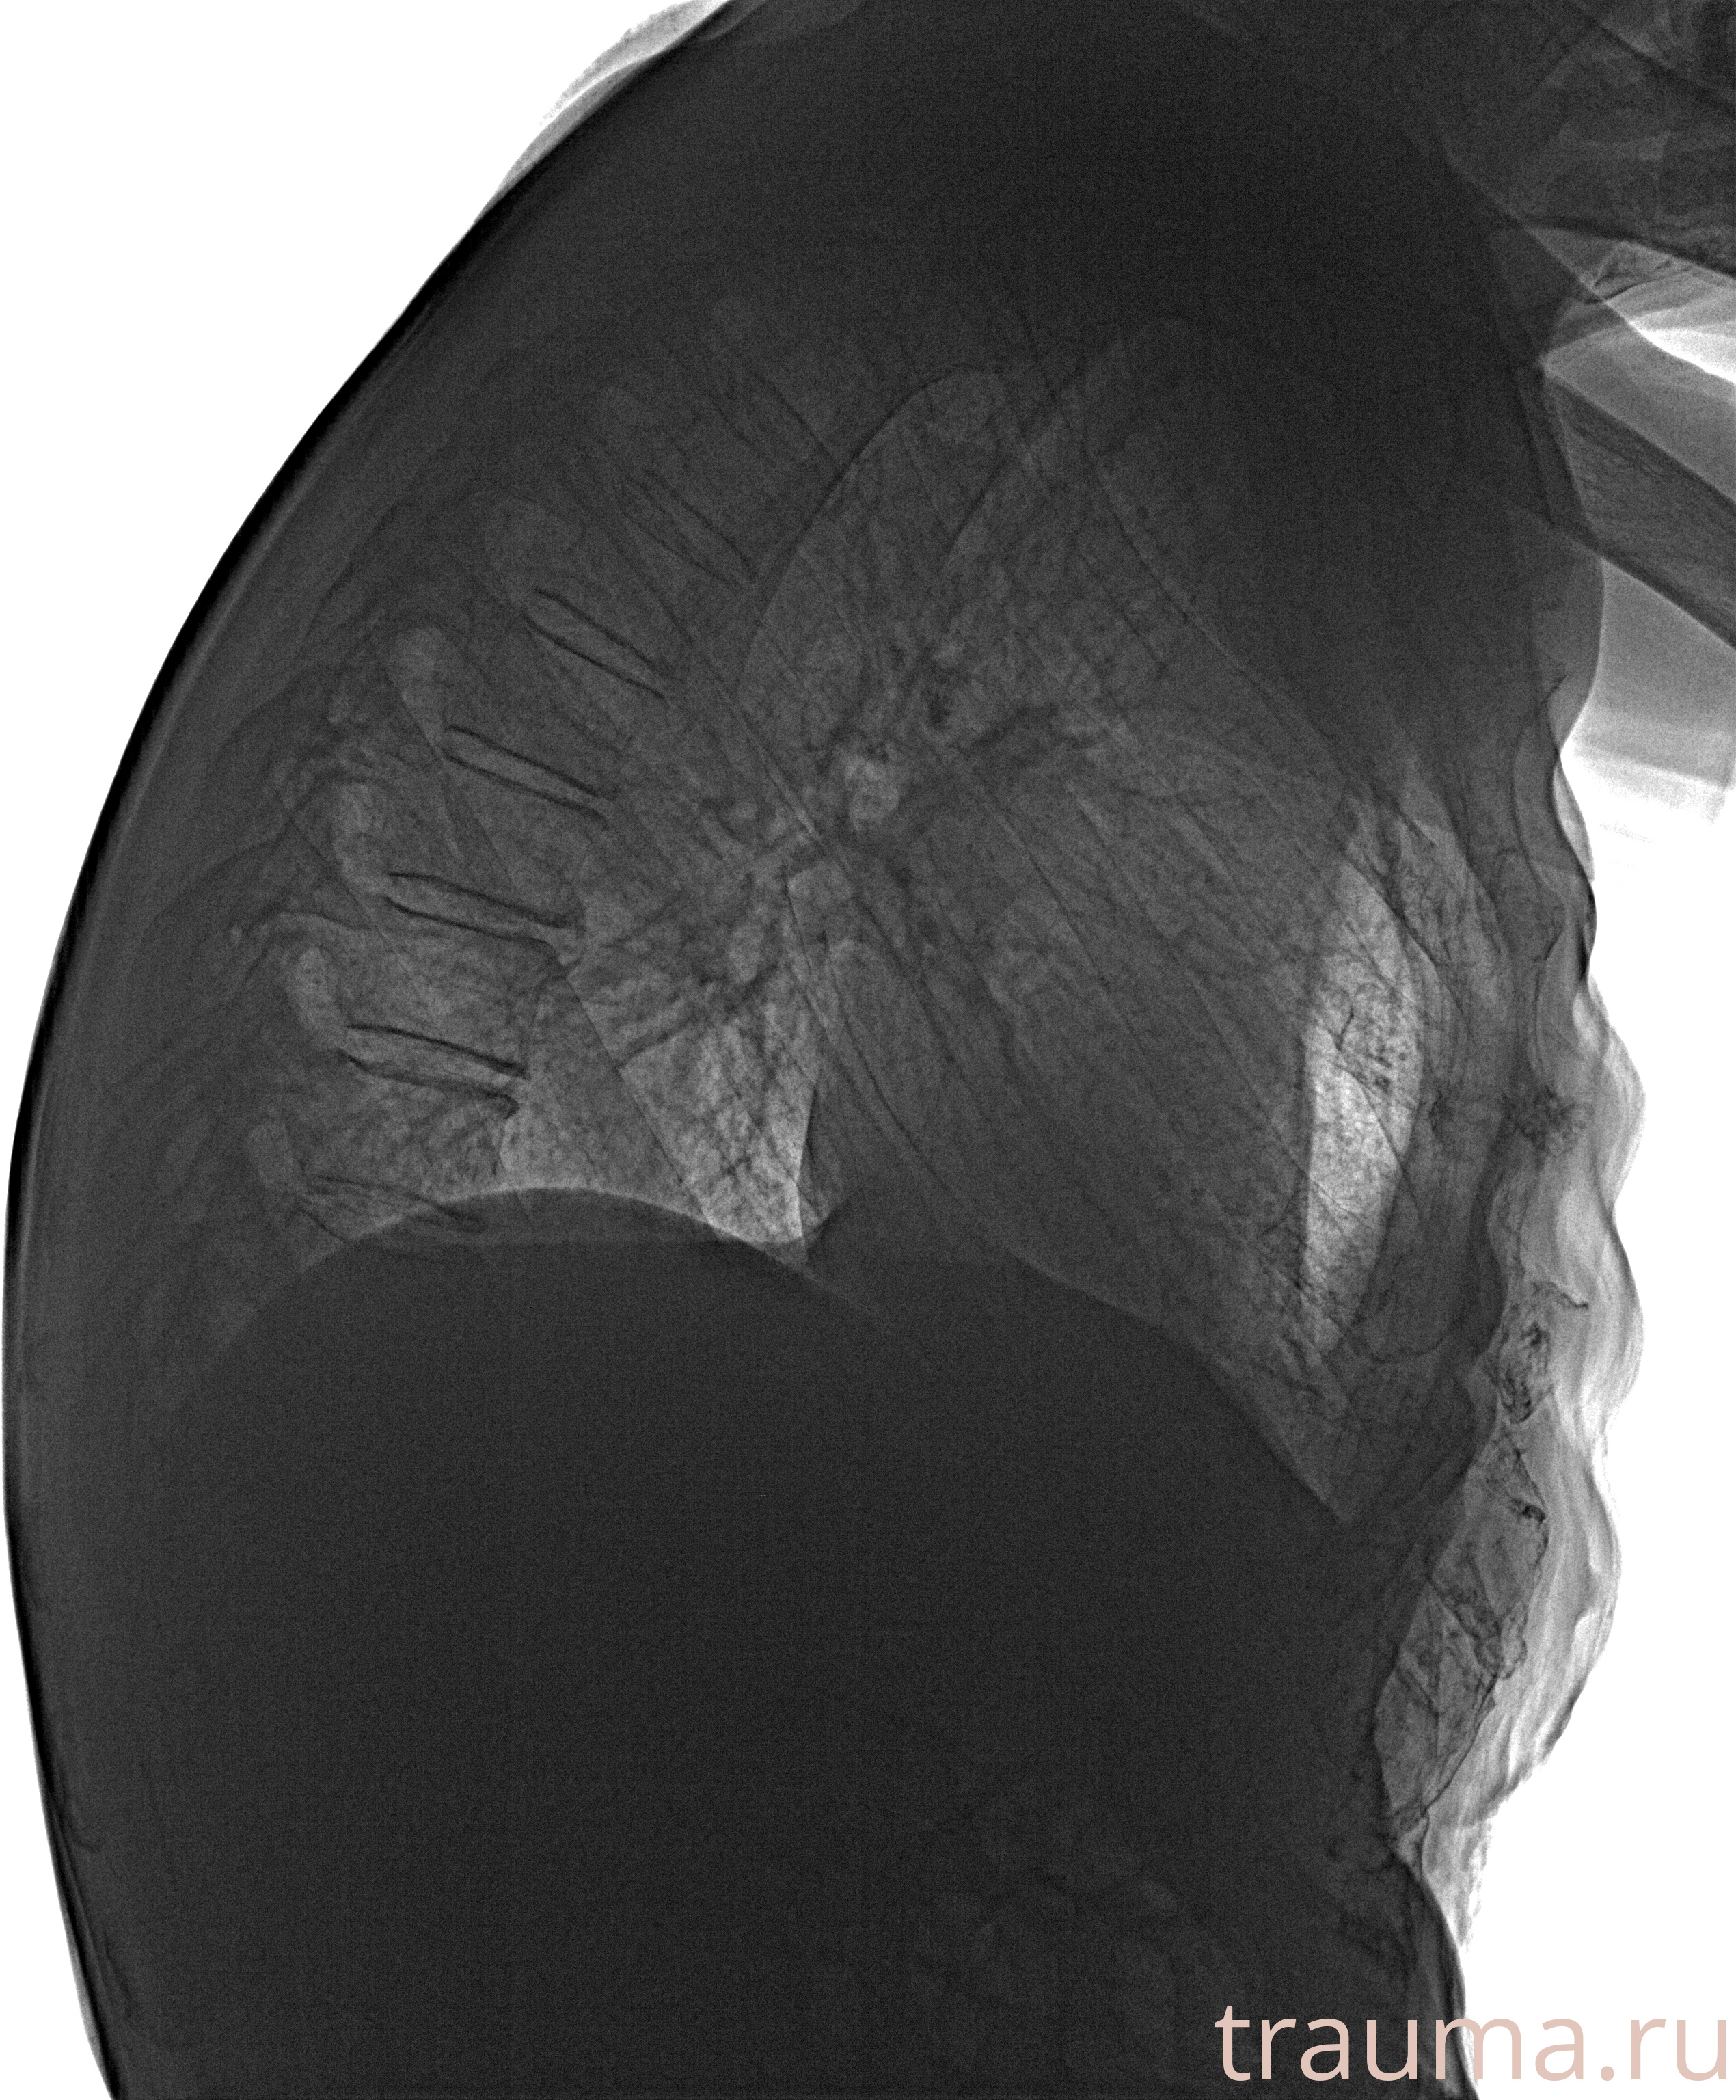

Рентгенограммы

Рентген на дому: по вашему адресу приезжает врач-рентгенолог, травматолог-ортопед с мобильным рентгеновским аппаратом, проводит диагностику травмы или заболевания, делает необходимые рентгенограммы, дает рекомендации по дальнейшему лечению. Получить качественные снимки в домашних условиях возможно благодаря уникальной методике, разработанной МосРентген Центром для института  Склифосовского